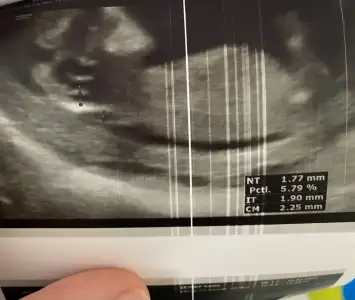

Bugün devlet Hastanesi'ne randevum vardı kızlar. İkili test sonucuma kan tahlillerime falan baktı herşey yolunda. Prilam'ı sordum ne kadar daha kullanılabilir diye mecbur kalırsan doğuma kadar bile kullanabilirsin sorun olmaz dedi rahatladım. Çok kusuyor musun ilaç yazayım öyleyse dedi kusma olmadığını söyleyince prilama devam dedi. Cinsiyet görünüyor mu deyince biraz uğraştı bacak arasını gördü pipi görmüyorum kız dedi ☺️kesinleşti yani ama ben yine de 16 haftayı beklemek istiyorum 2 hafta sonra da özelde randevum var orda netleşir iyice inşallah🥰